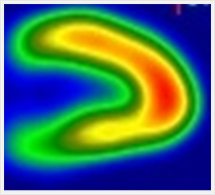

安静時心筋血流シンチグラフィ

心臓の筋肉に酸素や栄養を供給する冠動脈が狭窄または閉塞すると、心臓は虚血状態になり、心筋梗塞に陥ります。心筋細胞の状態(虚血部位、梗塞範囲)を調べる目的で行われる検査です。

1.前準備として食事・水分の制限は特に必要ありません。

2.心筋血流シンチグラフィ用の検査薬を静脈注射します。

3.検査薬が心臓の筋肉に集まるのに約30分かかるため、注射後30分経てから撮影を開始します。

4.検査薬は肝・胆道系から排泄されるため、妨げにならないように検査開始直前に必ず水分を少し摂取していただきます。

5.撮影時間は約30分かかります。

6.健康な心臓の筋肉には通常良く集まり、障害がある場合はその障害の程度に応じた集積の低下がみられます。